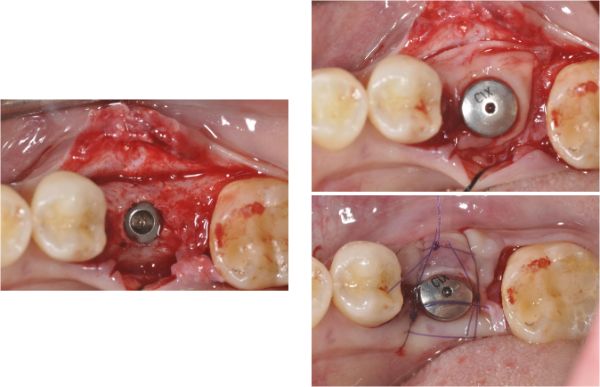

植牙補骨(PRF)

6個月後植體逐漸穩定